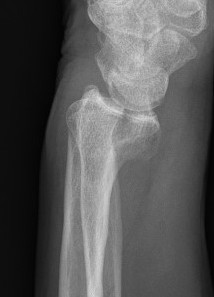

Colle's Fracture

- distal radial fracture with dorsal displacement